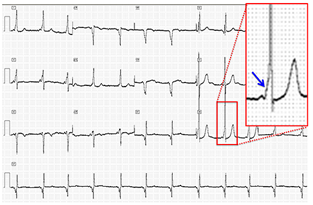

Once identified and appropriately treated, WPW syndrome is associated with an excellent prognosis, including the potential for permanent cure through catheter ablation. Asymptomatic patients with only pre-excitation on ECG generally have a very good prognosis. Patients with a family history of Sudden Cardiac Death or significant symptoms of tachyarrhythmias have worse prognoses. However, even in patients with asymptomatic WPW, the risk of Sudden Cardiac Death is increased above that of the general population. Some studies hypothesized that 2 mechanisms are involved in the pathogenesis of AF in patients with Wolff-Parkinson-White syndrome: one is related to the abnormal pathway that predisposes the atria to fibrillation, and the other is independent from the abnormal pathway and is related to increased atrial vulnerability present in these individuals.4,5 According to the literature, risk factors for the development of AF in the setting of WPW syndrome include advancing age (2 peak ages for AF occurrence are recognized, one at 30years and the other at 50years), male gender, and prior history of syncope (Figure 4 & 5).

Figure 4 Wolff-Parkinson-White (ECG 12 Leads).

Figure 5 Detail on V3.

A Wolff-Parkinson-White during sinus rhythm. Negative delta wave in V1 and positive in V5, with a short PR-interval. On the right, an episode of atrial fibrillation with high pre-excitation in the same leads, symptomatic for syncope and need immediate electrical cardioversion. The first three rows correspond to the DII electrocardiographic leads V1 and V5, and the following four intracavitary proximal AV junction, AV junction distal ablation catheter and right ventricle (Figure 6). In many more occasions that we can think, Wolff-Parkinson-White can go together to other cardiac electrical disease.10 The cryptogenic Wolff-Parkinson -White is not uncommon. We will put two graphic examples.